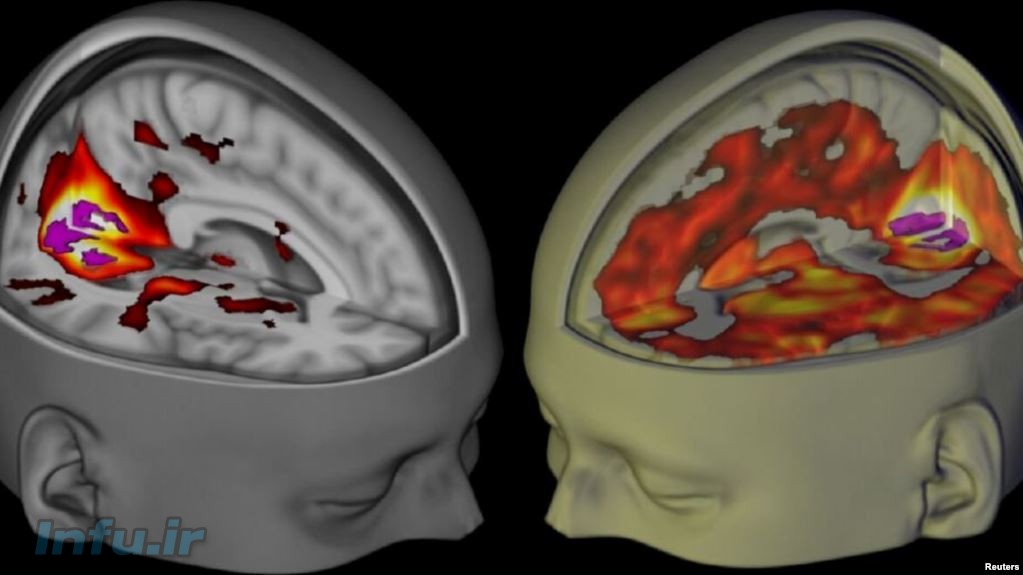

دانشمندان برای نخستین بار مغز افراد تحت تاثیر ال اس دی اسکن کردهاند. آنها دریافتهند که این ماده روانگردان مغز را «رها» کرده و باعث میشود که مغز بزگسالان «مانند مغز نوزادان» کار کند.

به گزارش خبرگزاری رویترز، یک تیم تحقیقاتی به مدیریت دانشمندان کالج امپریال لندن، میگوید که شبکههای مختلف مغز، در حال عادی از هم جدا و مستقل کار میکنند. به عنوان مثال فعالیتهایی از قبیل دیدن، حرکت و شنیدن توسط شبکههایی از هم مستقل در مغز اتفاق میآفتد اما در هنگام مصرف ال اس دی، این جدایی بین شبکهها از بین میرود و فعالیت مغز بیشتر شبیه به یک سیستم واحد میشود.

نتایج این تحقیق که در مجله علمی نشنال آکادمی آف ساینس منتشر شده نشان میدهد که در مغز داوطلبانی که این آزمایش بر روی آنها انجام شده، بسیاری از ناحیههای مغزی که در حال عادی ربطی به بینایی ندارند، هم در پردازش بصری مشارکت میکنند. دانشمندان میگویند که این میتواند توجیهی برای وجود توهم پیچیده بصری باشد که افراد در هنگام مصرف ال اس دی با آن روبهرو هستند.